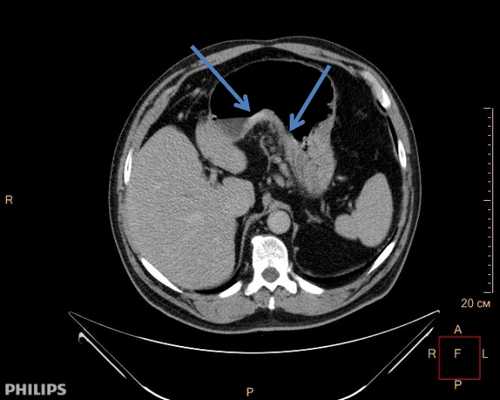

Мультиспиральная компьютерная томография (МСКТ) с внутривенным контрастированием является обязательным методом диагностики рака пищевода. Необходимо выполнять МСКТ как органов грудной клетки, так и брюшной полости. МСКТ обязательно надо выполнять с внутривенным введением контрастного вещества, так как опухоль и лимфатические узлы накапливают рентгеноконтрастный радиофармпрепарат. Проведение исследования без контрастного вещества не информативно. Мультиспиральная компьютерная томография позволяет определить точные верхние и нижние границы опухоли, глубину прорастания опухоли в стенку пищевода, распространение опухоли на соседние органы и структуры. Так же по результатам исследования можно сделать выводы о наличии поражения регионарных лимфатических узлов (наличие метастазов), а так же о вторичном распространении (метастазировании) опухоли в органы мишени (печень, легкие, кости скелета и др.). Результаты МСКТ принципиально важны для правильного стадирования опухолевого процесса и определения дальнейшей тактики лечения, решения вопроса о возможности выполнения радикального хирургического вмешательства.